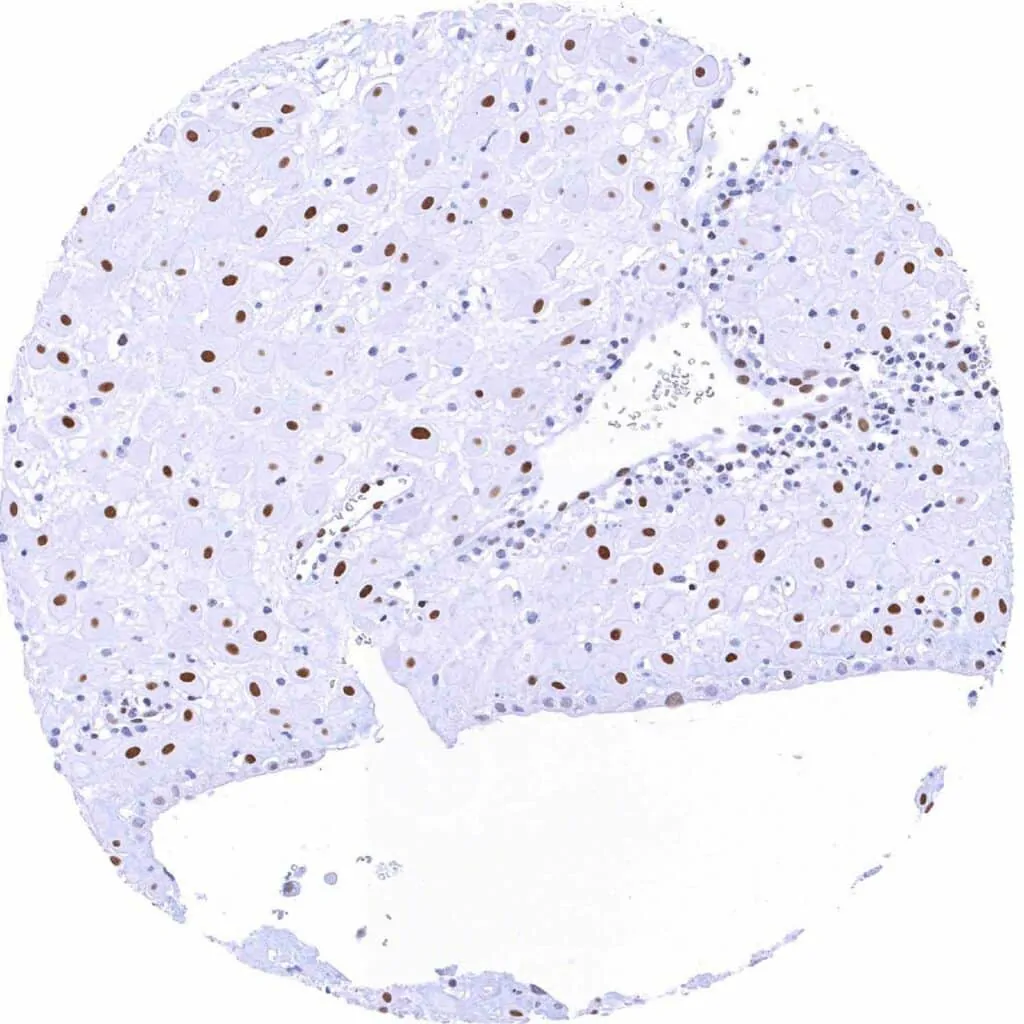

Liver – Weak to moderate TLE1 staining of bile duct cells. Faint staining of hepatocytes

Pancreas – Weak to moderate TLE1 staining of acinar and ductal cells

Pancreas – Weak to moderate TLE1 staining of acinar cells and of most islet cells